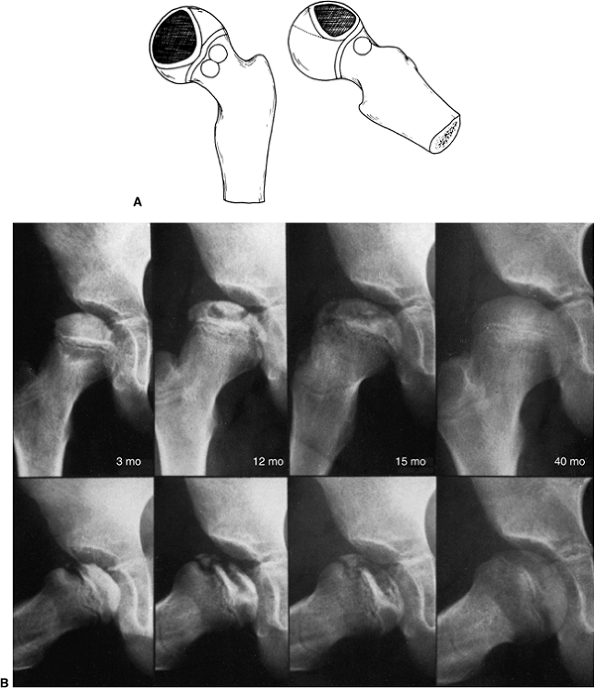

of recurrent Perthes disease (118,119) (Fig. 25.2). Salter and Thompson (120,121)

A girl, 4 years and 8 months of age, was treated for left hip Perthes disease (late fragmentation phase) beginning in January 1983. Anteroposterior (right, A–I) and Lauenstein (see pg. 1044, A–I) views of the right hip at different stages, January 1983 to December 1987. A: View of the right hip at the time of initial presentation with no signs of involvement (January 1983). B: Early involvement, patient still asymptomatic (September 1983). C–F: Progressive healing of the right femoral epiphysis at May 1984 (C), August 1984 (D), May 1985 (E), and November 1985 (F). G: Femoral head was completely healed by December 1986. H: Recurrent changes in the density of the femoral head and a subchondral fracture that involves less than 50% of the head (Catterall group 2) was seen in June 1987. I: Complete involvement of the ossific nucleus (Catterall group 4) with diffuse metaphyseal reaction and cysts in December 1987. (From Martinez AG, Weinstein SL. Recurrent Legg-Calvé-Perthes’ disease: case report and review of the literature. J Bone Joint Surg Am 1991;73:1081.) |